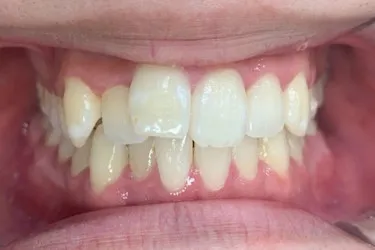

人と接する機会が多く、第一印象を大切にしたいと考え、写真写りや笑顔への自信を高めたいという思いから矯正を決意された矯正当時学生だった22歳男性の H.S.様に、スマイルモア矯正を選んだ理由を伺いました。

| 詳細情報 | |

|---|---|

| 費用 | 360,000円(税込396,000円) |

| 治療期間 | 11ヶ月 |

| 治療内容 | マウスピースを用いた歯列矯正 |

| 追加処置 | IPR |

以前よりも歯並びが改善され、人とコミュニケーションをとることに自信がつきました。 「スマイルモア」という名前の通り、笑顔に自信がついたことで今までよりも口を開けて笑う機会も増えました。 矯正期間が年単位だったのですぐに変化があったわけではないですが、綺麗な仕上がりに満足しています。